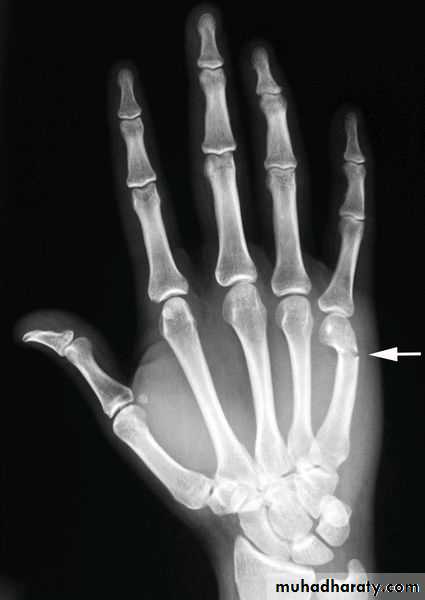

Metacarpal fractures:

Fracture of metacarpal shaft: transverse or spiral

Fracture of the metacarpal neck: usually of the 5th finger (boxer's fracture), localized swelling with flattening of the knuckle.Fracture of the metacarpal base.